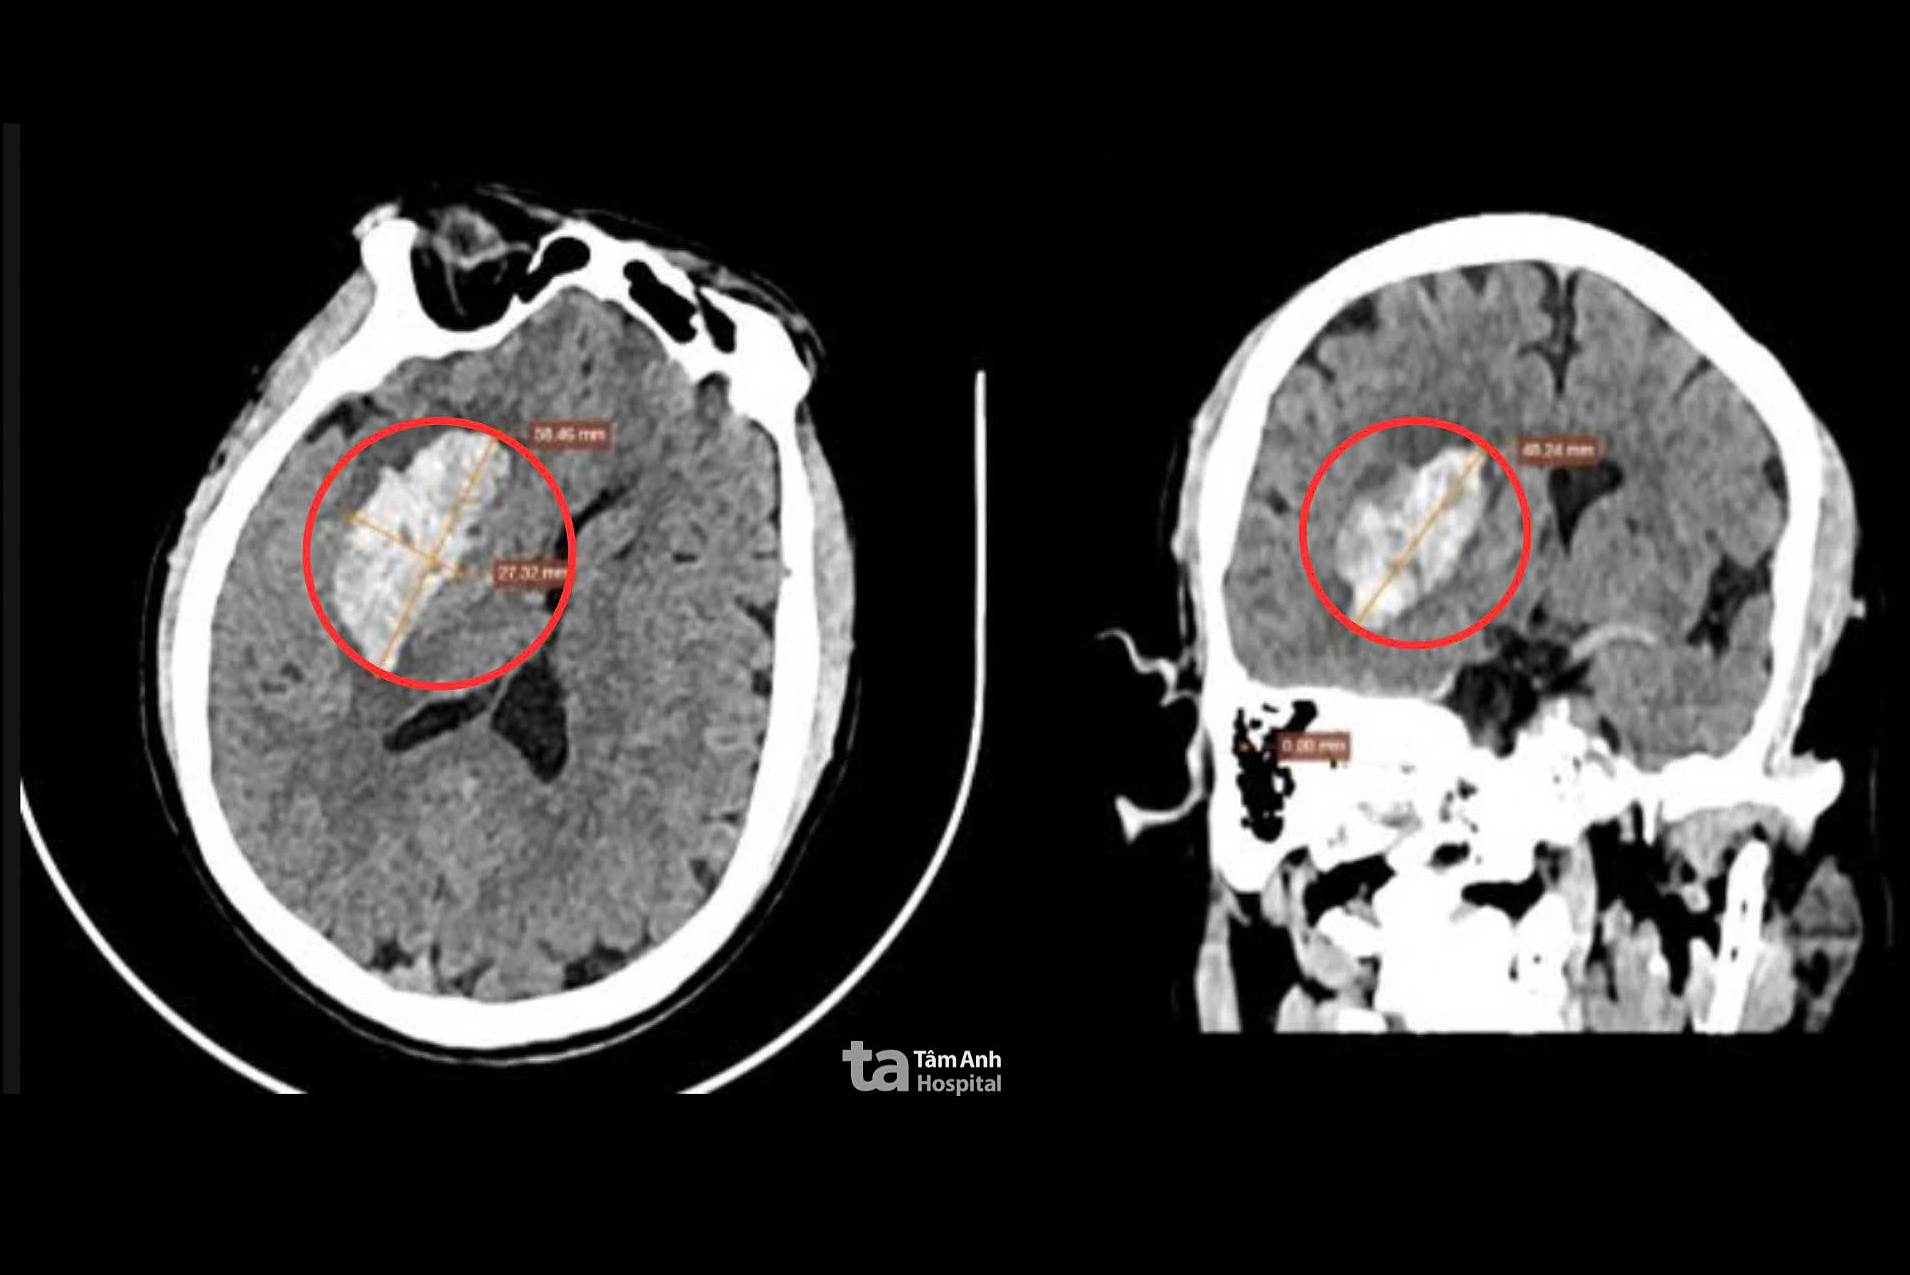

Nghia experienced a sudden, severe headache, collapsed, and developed left-sided weakness and slurred speech. His family rushed him to a local hospital. A CT scan revealed a right-hemisphere brain hemorrhage, prompting his transfer to Tam Anh General Hospital in TP HCM for intervention. Upon arrival, Nghia's blood pressure was high (153/94 mmHg), his left arm strength was 2/5, his left leg strength was 3/5, and his consciousness was declining. Imaging showed a roughly 6 cm hematoma in his right brain causing cerebral edema, compressing the right lateral ventricle, and shifting the midline 4 mm to the left.

A CT scan revealed a large hemorrhage in Nghia's brain. Photo: Tam Anh General Hospital

Post-surgery, Nghia was conscious and didn't require intensive care. His incision was clean and dry. Three days later, he showed good recovery, improved consciousness, and regained leg movement. A follow-up CT scan confirmed complete hematoma removal, with only slight ventricular compression and a normalized midline. Nghia's vital signs were closely monitored to prevent re-bleeding. After managing his underlying conditions and stroke risk factors, he was discharged and continued rehabilitation with a personalized exercise plan.